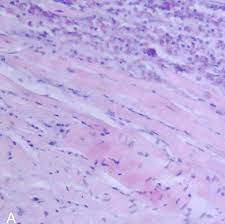

심근염(Myocarditis)은 심장 근육인 심근의 염증을 나타내며, 주로 바이러스, 박테리아, 기생충, 약물 반응 등의 인자로 인해 발생합니다. 이 염증은 심근 조직의 염증 세포와 면역 반응의 과도한 활성화로 인해 발생할 수 있습니다. 심근염은 심장 기능의 변화를 초래하며, 심장 파괴와 심부전과 같은 심각한 합병증을 유발할 수 있습니다.